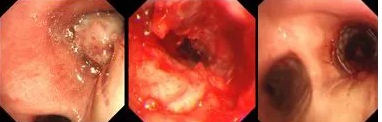

原來,秦爺爺入院時診斷為“右主支氣管”鱗狀細(xì)胞癌伴壞死。他的右主支氣管被腫瘤完全堵塞,混合性狹窄。面罩吸氧10升/分的狀況下,指脈氧只有85%,無法平躺,呼吸困難,病情十分危急,隨時有生命危險。

經(jīng)評估并與家屬溝通同意后,歐陽海峰副院長決定為患者實施TTS氣道支架手術(shù)。手術(shù)當(dāng)天,在麻醉手術(shù)中心的配合下,歐陽海峰副院長為患者在局麻下快速凍切腫瘤組織,實現(xiàn)右主支氣管再通,并經(jīng)氣管鏡活檢孔道迅速植入14*30 TTS支架一枚。支架植入過程耗時僅6秒,迅速緩解了患者的氣短瀕死癥狀。